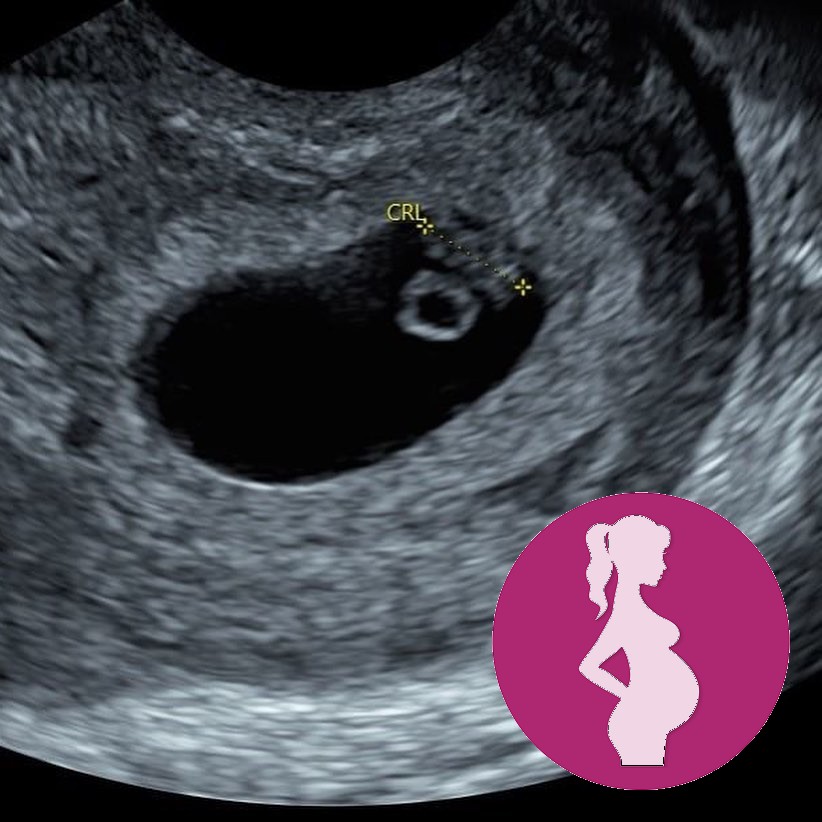

We offer early scans from 7 weeks of pregnancy.

If you come before this gestation it can be TOO EARLY to detect a fetal heart beat and cause you unnecessary concern.

➡️This is because the embryo is the third structure to be visualized using ultrasound in an early pregnancy!

➡️Around 5.5 -6 weeks gestational age the embryo appears as only a 2-3 mm focal thickening at the periphery of the yolk sac, and heart activity may still be undetectable. .

➡️This pattern is termed the “diamond ring” 💍 sign. This appearance is given by the yolk sac, which represents the “ring” and the tiny early embryo located on the outside representing the “diamond”. This is the earliest sign of embryonic development.